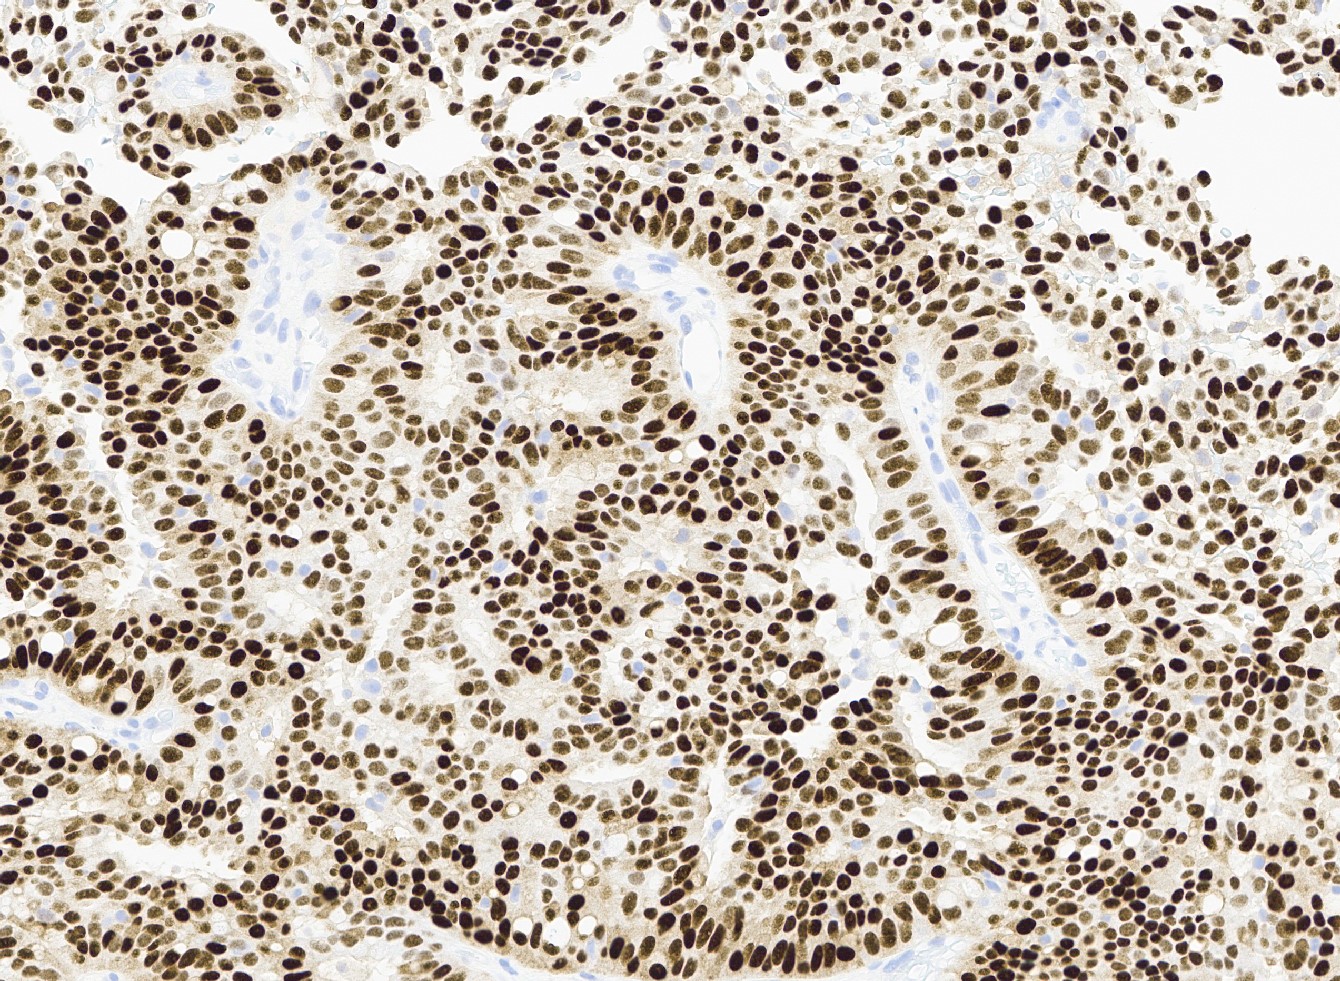

- Most show complete lack of myoepithelial cells along the papillae and around the periphery of the tumor (Am J Surg Pathol 2006;30:1002, Am J Surg Pathol 2011;35:1)

Positive stains

- ER and PR (strong, diffuse) (Curr Probl Cancer 2018;42:291, Mod Pathol 2021;34:1044)

Negative stains

- Myoepithelial markers (i.e., p63, calponin, actin, smooth muscle myosin heavy chain, CD10) negative within papillae and around the tumor or focally present at the periphery of the lesion (Am J Surg Pathol 2006;30:1002, Am J Surg Pathol 2011;35:1, Curr Probl Cancer 2018;42:291)

Microscopic (histologic) images

Contributed by Kristen E. Muller, D.O. , Mariel Molina Nunez, M.D. and Julie Jorns, M.D. (Case #518)